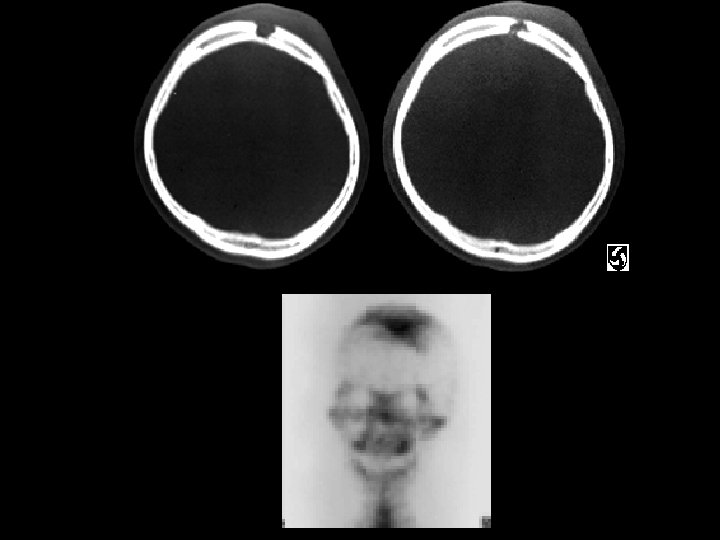

Femoral Head AVN • Findings: – bilateral femoral head AVN w/o collapse – right pelvic renal tx